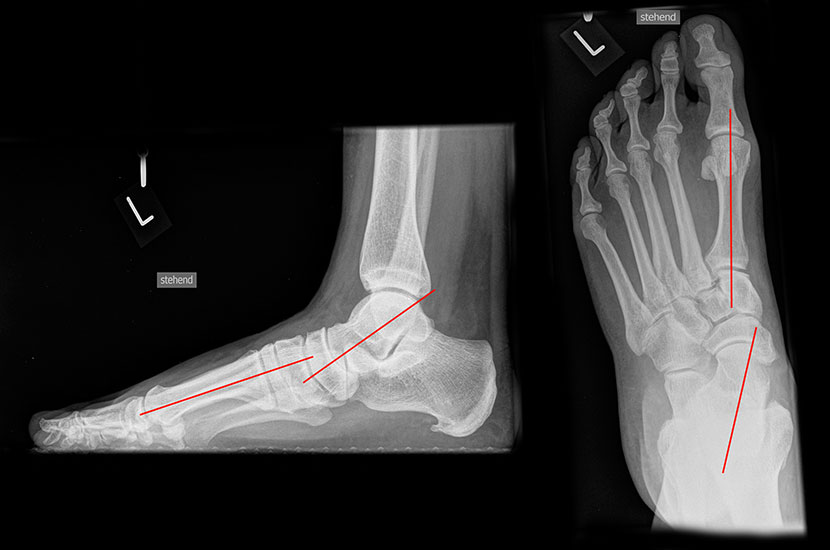

Röntgenaufnahmen des Fußes d.p., streng seitlich und schräg unter Belastung. Saltzmann Aufnahme zur Beurteilung der Rückfussachse.

Operationsplanung anhand der Röntgenaufnahmen unter Beachtung wichtiger radiologischer Landmarks wie Rückfussachse, Metatarsale I – Talushals-Achse im dp und lateralen Strahlengang (Abbildung 1 und 2).

Abbildung 1

Abbildung 2